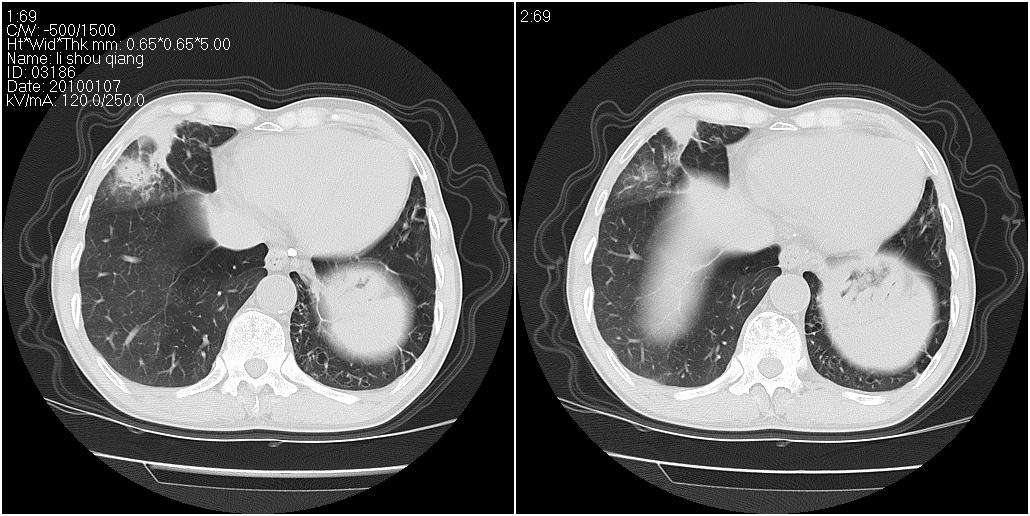

标题: CT24038:男性,58岁。主因咳嗽带血性CT检查。 [打印本页]

标题: CT24038:男性,58岁。主因咳嗽带血性CT检查。

右肺中叶外侧段可见团块影,外形不规则,内见空泡征。左下肺见蜂窝状低密度透亮影,部分层面主动脉旁瘤样突出。考虑右肺中叶外围型肺癌可能性大,左下肺支气管扩张,主动脉弓瘤样突出。

考虑右肺癌可能性大,左下肺支气管扩张,主动脉弓瘤样突出?建议增强

3、建议增强除外主动脉弓息室样动脉瘤。

3、建议冠状位重建除外主动脉弓息室样动脉瘤。